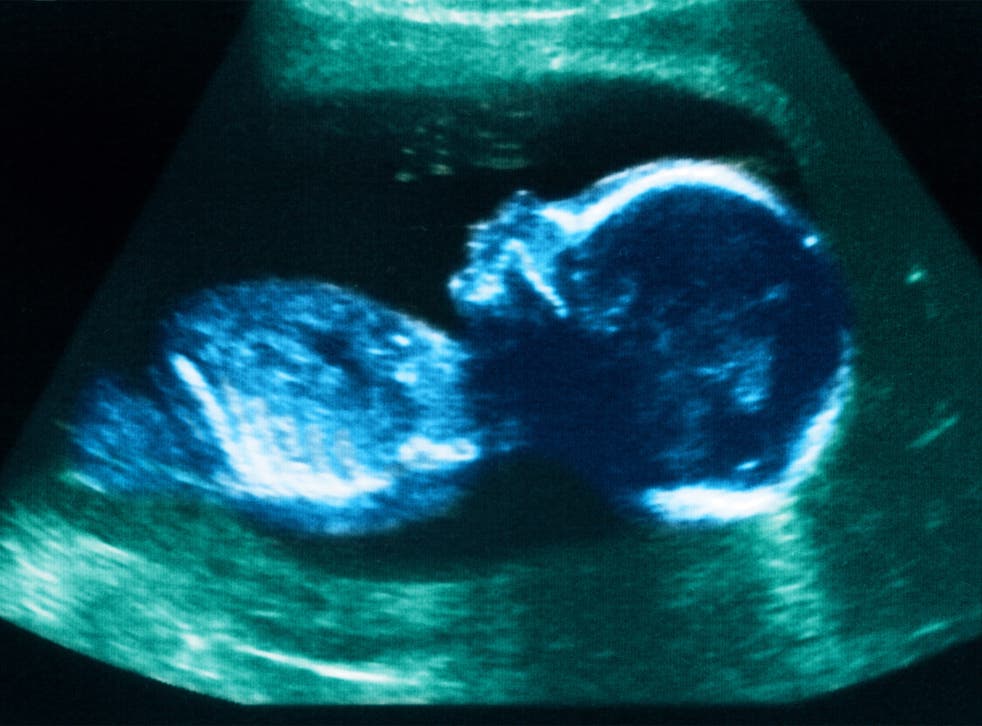

ഗർഭസ്ഥ ശിശുക്കളുടെ ലിംഗ നിർണയം, ഗർഭഛിദ്രം: 7 അംഗ സംഘം പിടിയിൽ

കോയമ്പത്തൂർ • ഗർഭസ്ഥശിശുക്കളുടെ ലിംഗ നിർണയം നട ഗർഭഛിദ്രം നടത്തുന്ന സംഘത്തിലെ 3 സ്ത്രീകളടക്കം 7 പേരെ ധർമപുരി പൊലീസ് അറസ്റ്റ് ചെയ്തു. തിരുപ്പത്തൂർസ്വദേശികളായ എം. ജ്യോതി (37), കെ സതീഷ് കുമാർ (37), സുധാകർ (37), ധർമപുരി സ്വദേശികളായ പി.കർപകം (38), സരിത (40), കുമാർ (38), എസ്. വെങ്കടേശൻ (33) എന്നിവരെയാണ് അറസ്റ്റ് ചെയ്തത്.

ഗ്രാമ പ്രദേശങ്ങളിലെ ഗർഭിണികളെ, അവരുടെ വീടുകളിലെ അൾട്രാ സൗണ്ട് മെഷീൻ ഉപയോഗിച്ചു പരിശോധിക്കുന്ന സംഘം ഗർഭസ്ഥ ശിശു പെണ്ണാണെന്നു തിരിച്ചറിഞാൽ വെങ്കടേശന്റെ വീട്ടിലെത്തിച്ചു ഗർഭാചിദ്രം നടത്തുകയായിരുന്നു രീതിയെന്നു പൊലീസ് പറഞ്ഞു. സ്കാനിങ്ങിന് 500 രൂപയും ഗർഭഛിദ്രത്തിന് 3,000 രൂപയുമാണ് ഈടാക്കിയിരുന്നത്.